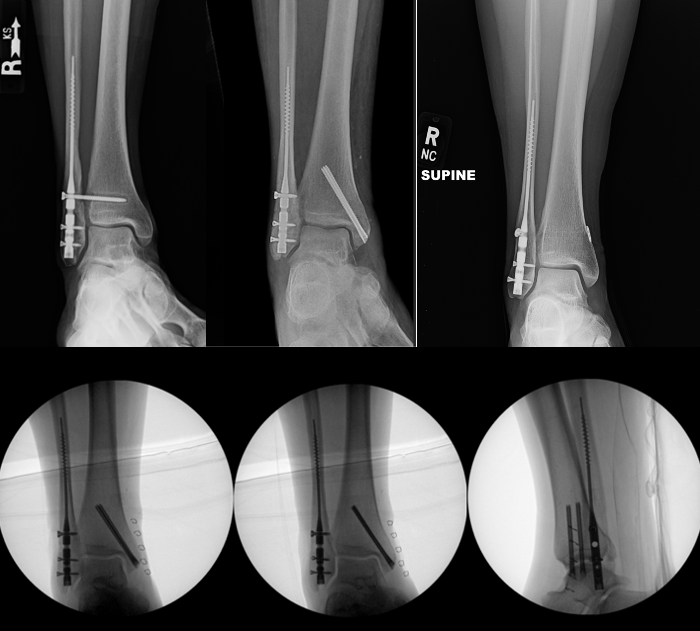

Standard Radiographs. Initial evaluation includes standard anteroposterior, lateral, and mortise radiographic views. Important findings to suggest tibiotalar joint instability include: talar shift or tilt, widened medial clear space (>4 mm or asymmetry compared with the contralateral clear space), fibular shortening or malrotation, and posterior malleolar displacement affecting joint congruency (Figure 1).

Stress Radiographs. Gravity or external rotation stress radiographs traditionally assess deltoid ligament integrity, particularly in isolated Weber B fractures. However, multiple studies demonstrate stress radiographs may overestimate instability, which may identify partial deltoid injuries that do not translate into functional ankle instability (Figure 2).3-5

Weight-Bearing Radiographs. More recent literature supports weight-bearing radiographs as a reliable and clinically relevant method to assess functional stability in select ankle fractures, particularly isolated Weber B injuries. Prospective studies show that patients with stable weight-bearing mortise alignment experience excellent outcomes with nonoperative treatment, even when stress views suggest instability.4-8 Although, a recent study by Zonneveld and Hoogendoorn in 2024 found substantial variability in the amount of weight-bearing on an ankle during weight-bearing radiographs, and to keep this information in mind when determining a treatment course.9